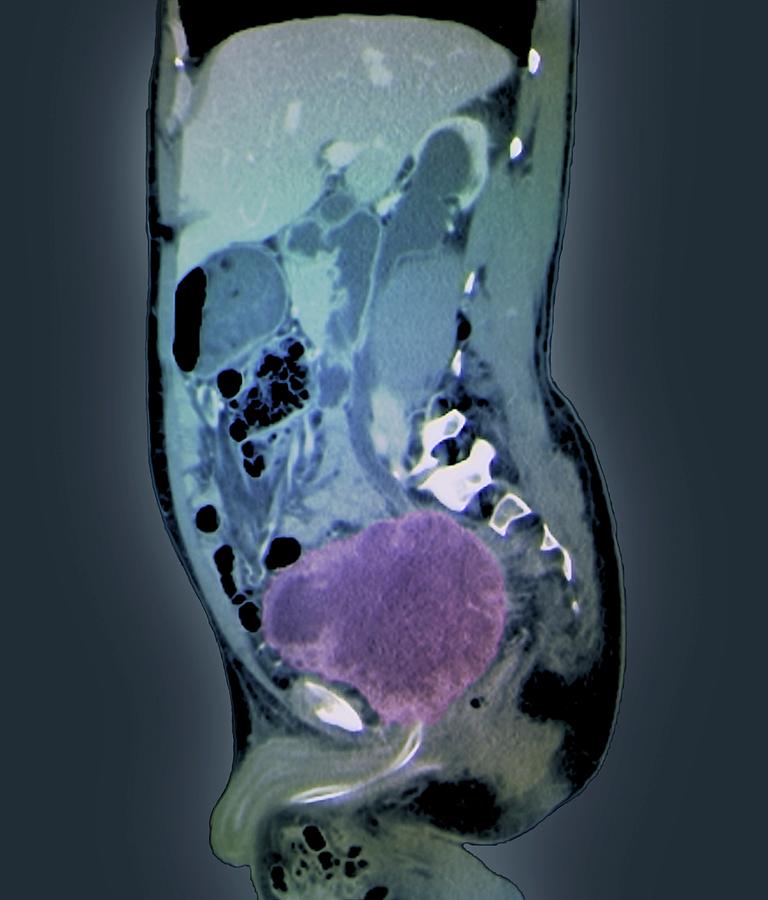

Bladder Cancer Photograph by Zephyr/science Photo Library – Pixels

CT scan showing the location of bladder tumor. | Download Scientific …

Urothelial carcinoma of the bladder in a 59-year-old man. CT image …

Bladder Cancer with CT Urography – Genitourinary Case Studies – CTisus …

CT scan of Case 1: bladder cancer mass with associated left …